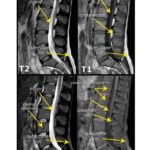

What is an MRI Lumbar Spine with Contrast?

MRI Lumbar Spine with Contrast is a specialised imaging technique that uses magnetic resonance imaging (MRI) to get detailed images of the lower back and its surrounding tissue. It is helpful in diagnosing conditions like bone problems, soft tissue issues, spinal cord issues, disc problems, severe back pain, birth defects and nerve issues.